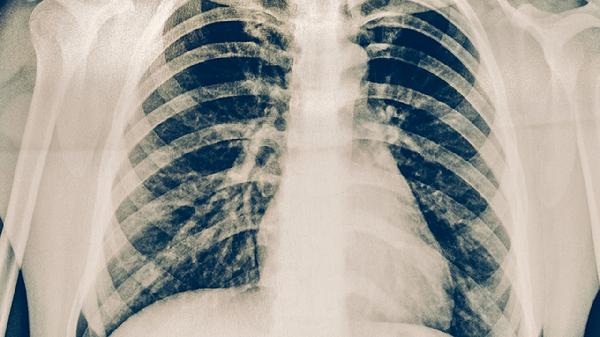

肺结核病有哪些预防措施

肺结核病的预防措施主要有接种卡介苗、避免接触传染源、增强免疫力、规范治疗感染者、改善居住环境等。肺结核是由结核分枝杆菌引起的慢性传染病,主要通过呼吸道传播。